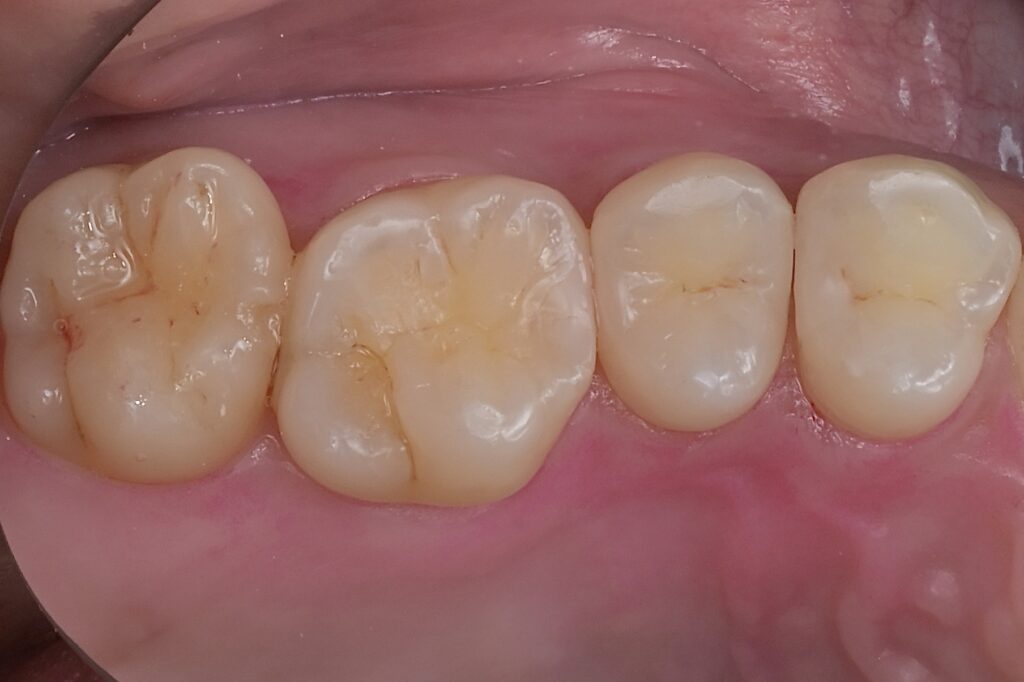

30代 虫歯治療 VPT(歯髄温存療法)ダイレクトボンディング #66

02虫歯治療(ダイレクトボンディング)

ダイレクトボンディングは、歯の欠損や小さな虫歯を即座に修復する方法です。歯と同色の材料を直接歯に盛り付け、自然な見た目と機能を取り戻します。